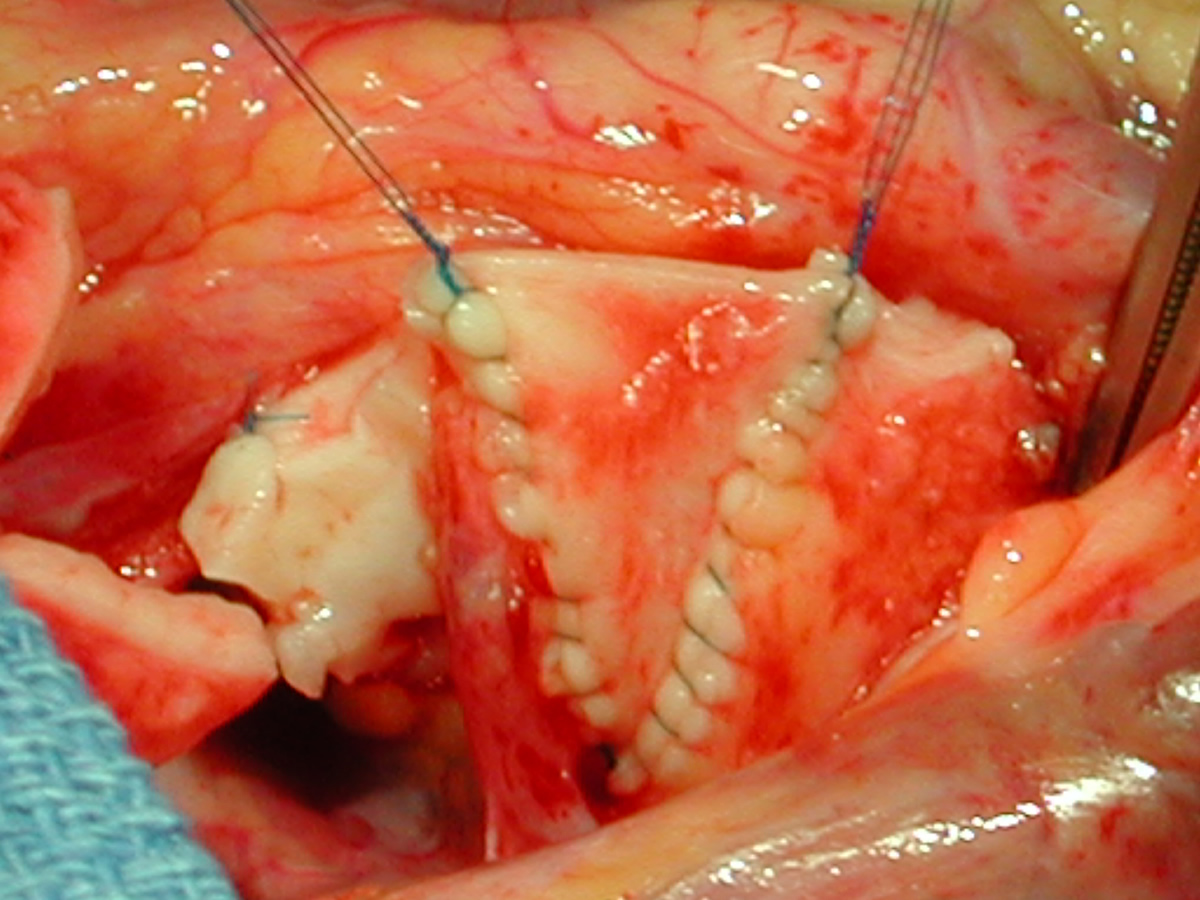

Figures 24 & 25: An incision is performed in the distal ascending aorta so that the orifice of the completed distal reconstruction will correspond in size to the proximal reconstructed aorta. Figures 26 & 27: A shield-shaped patch is being placed in the incision in the proximal ascending aorta – noncoronary cusp. Suturing is with 7-0 polypropylene suture. The patch should not be too wide, becaus this will lead to commissural stretching and loss of central coaptation with reultant aortic valve insufficiency.

Figures 28 & 29: Completed noncoronary cusp patch. Figure 30: A portion of thick intimal hyperplasia adjacent to the left coronary orifice is sharply resected with a no. 11 blade. Figure 31: Completed resection showing no residual intimal thickness.